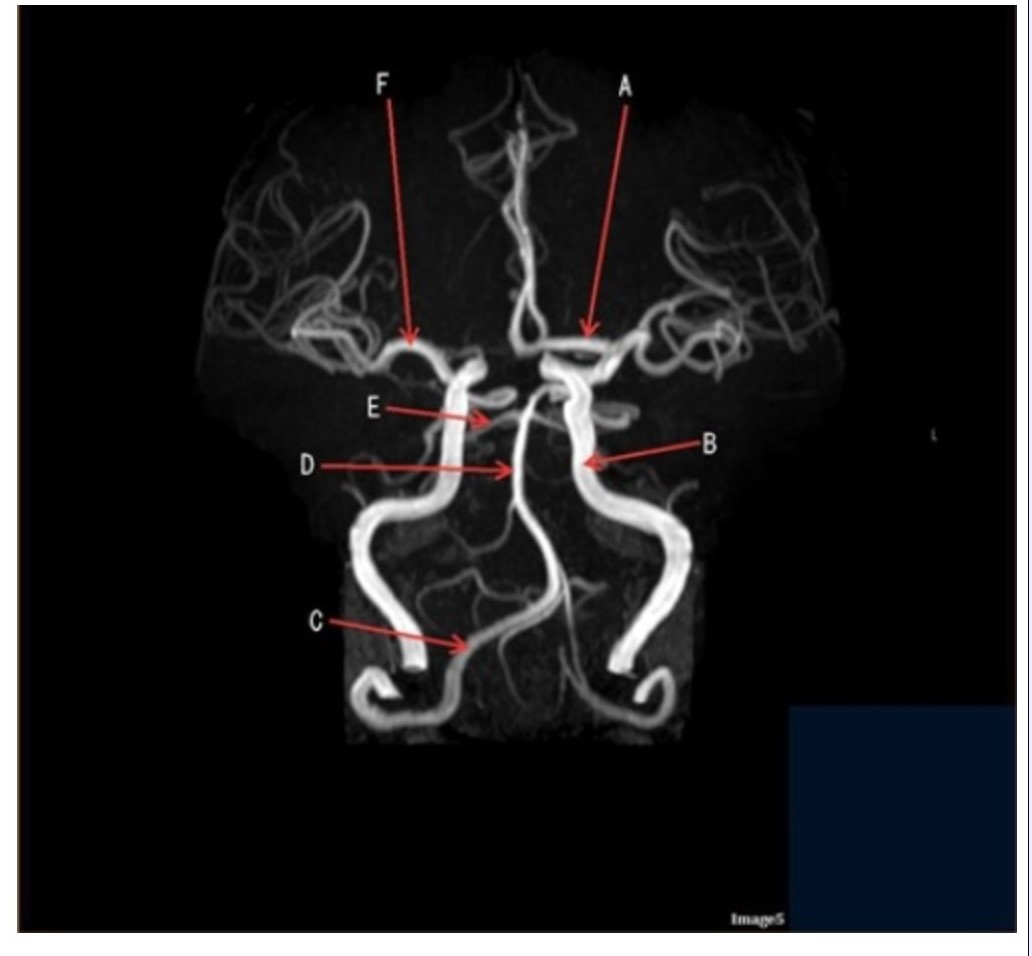

Letter D in Image 5 is pointing to:

A. Anterior cerebral artery

B. Internal carotid artery

C. Basilar artery

D. Posterior cerebral artery

E. Middle cerebral artery

Letter F in Image 5 is pointing to:

A. Anterior cerebral artery

B. Internal carotid artery

C. Basilar artery

D. Posterior cerebral artery

E. Middle cerebral artery

Image 5 is an example of an:

A. MRI brain

B. MRV sagittal sinus

C. MRS single voxel

D. MRA Circle of Willis

Letter B in Image 5 is pointing to:

A. Anterior cerebral artery

B. Internal carotid artery

C. Basilar artery

D. Posterior cerebral artery

E. Middle cerebral artery

Letter C in Image 5 is pointing to:

A. Vertebral artery

B. Internal carotid artery

C. Basilar artery

D. Posterior cerebral artery

E. Middle cerebral artery

Letter E in Image 5 is pointing to:

A. Anterior cerebral artery

B. Internal carotid artery

C. Basilar artery

D. Posterior cerebral artery

E. Middle cerebral artery

Letter A in Image 5 is pointing to:

A. Anterior cerebral artery

B. Internal carotid artery

C. Basilar artery

D. Posterior cerebral artery

E. Middle cerebral artery